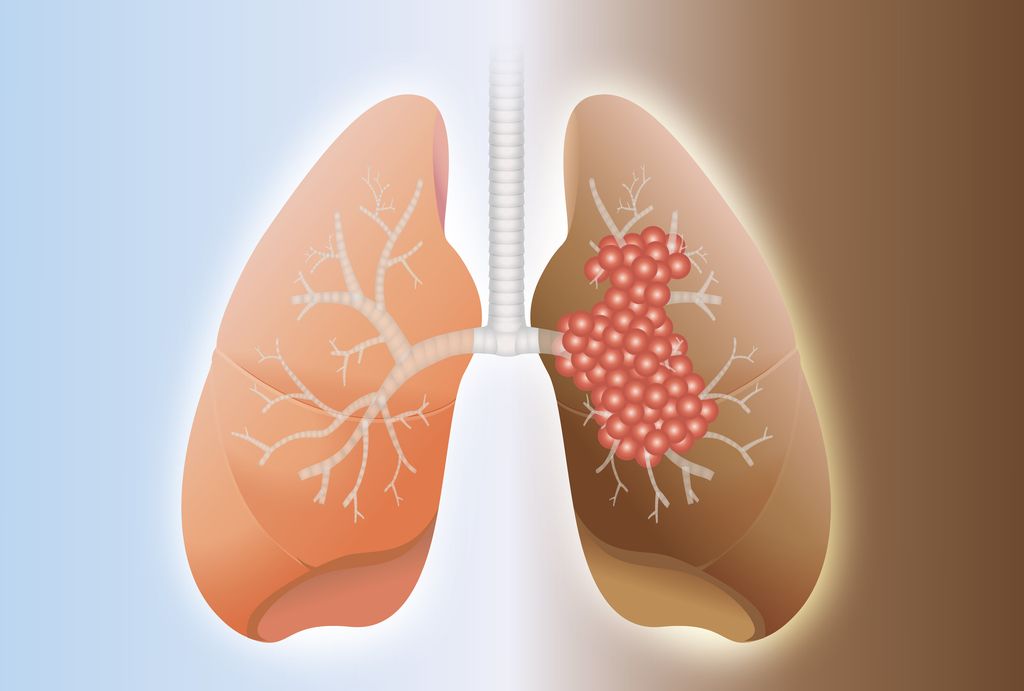

Здоровье дыхательной системы: бронхи и легкие